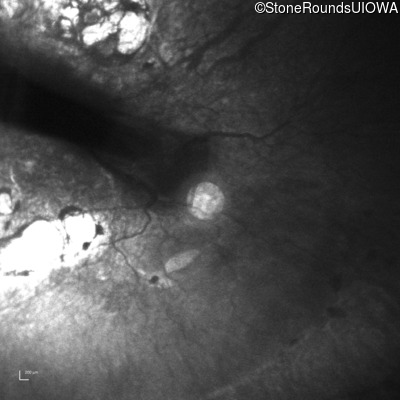

Infrared Fundus Photograph - Right - 20/500

Exemplar